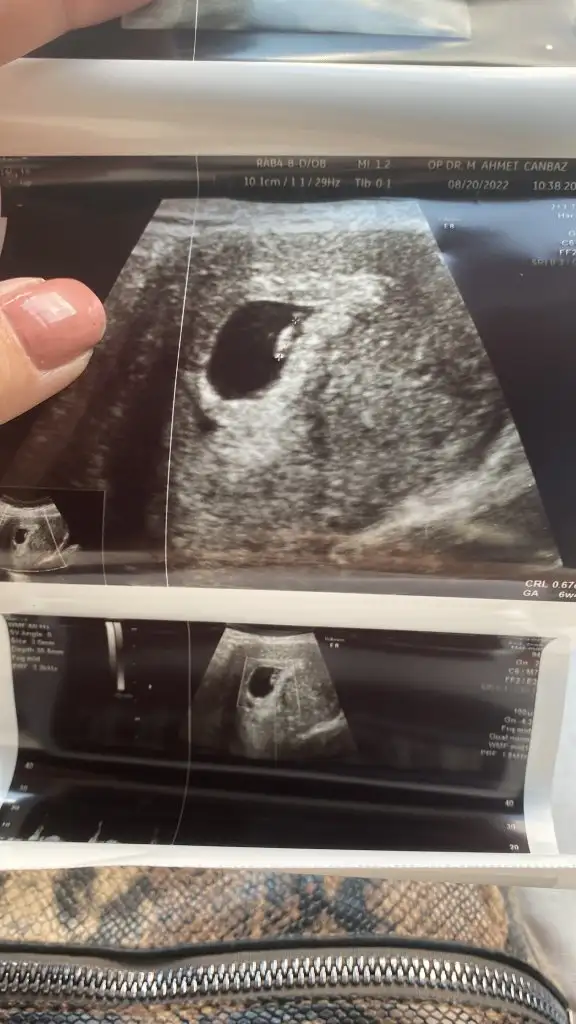

Kız benide ağlatdın..İn şa Allah bizlerde duyarız kuzumKızlar çıktım doktordan ayy şükürler olsun gayet iyiyiz kalp atıslarını duyduk allah ım nasıl bir duygu eşim agladıbende panik atak var benim kalp yerinden cıkcak doktor ddi bebekten cok suan senin kalp atıslarını duyuyorum dedi bu da minnosun resmi karından baktı ramzi teorisine bakın 3. Kare 7 eylülde bidaha cagırdı ense kemik omurgalarına bakalım dedi tekrar idrar testi verdim bide kan verdim gene baska değerlerede bakıcam ddi

Oyy ne kadar tatlı duruyor ordaKızlar çıktım doktordan ayy şükürler olsun gayet iyiyiz kalp atıslarını duyduk allah ım nasıl bir duygu eşim agladıbende panik atak var benim kalp yerinden cıkcak doktor ddi bebekten cok suan senin kalp atıslarını duyuyorum dedi bu da minnosun resmi karından baktı ramzi teorisine bakın 3. Kare 7 eylülde bidaha cagırdı ense kemik omurgalarına bakalım dedi tekrar idrar testi verdim bide kan verdim gene baska değerlerede bakıcam ddi

Maşallah çok sevindim adınaKızlar çıktım doktordan ayy şükürler olsun gayet iyiyiz kalp atıslarını duyduk allah ım nasıl bir duygu eşim agladıbende panik atak var benim kalp yerinden cıkcak doktor ddi bebekten cok suan senin kalp atıslarını duyuyorum dedi bu da minnosun resmi karından baktı ramzi teorisine bakın 3. Kare 7 eylülde bidaha cagırdı ense kemik omurgalarına bakalım dedi tekrar idrar testi verdim bide kan verdim gene baska değerlerede bakıcam ddi